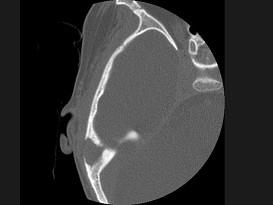

问题 女性,17岁,右耳乳突区隐痛,右耳后乳突区出现包块,逐渐增大,CT检查如图所示,请选择最可能的 ( )

选项 A、中耳癌 B、听神经瘤 C、化脓性中耳炎 D、嗜酸性肉芽肿 E、胆脂瘤

答案 D